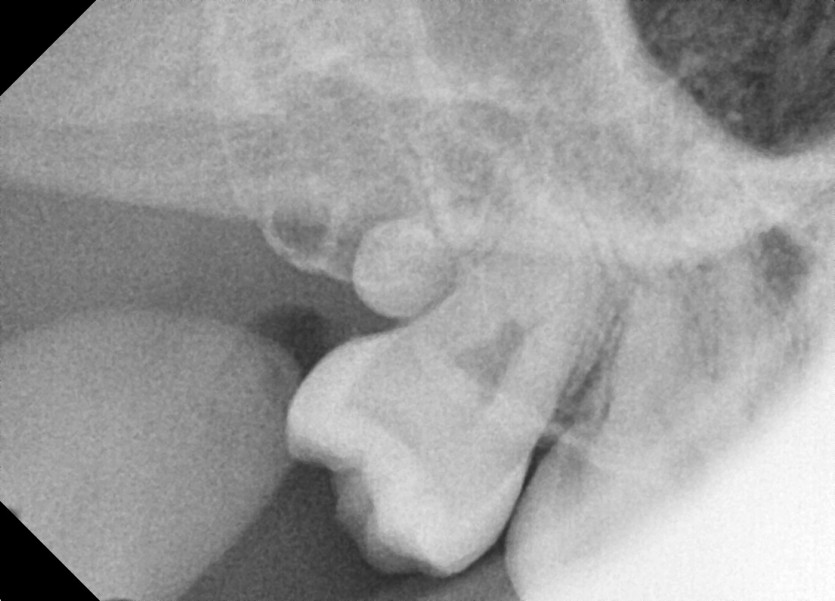

#18,28,38,48 사랑니 발치 (#19과잉치 포함)

구강 외과 전문의가 당일 발치했습니다.